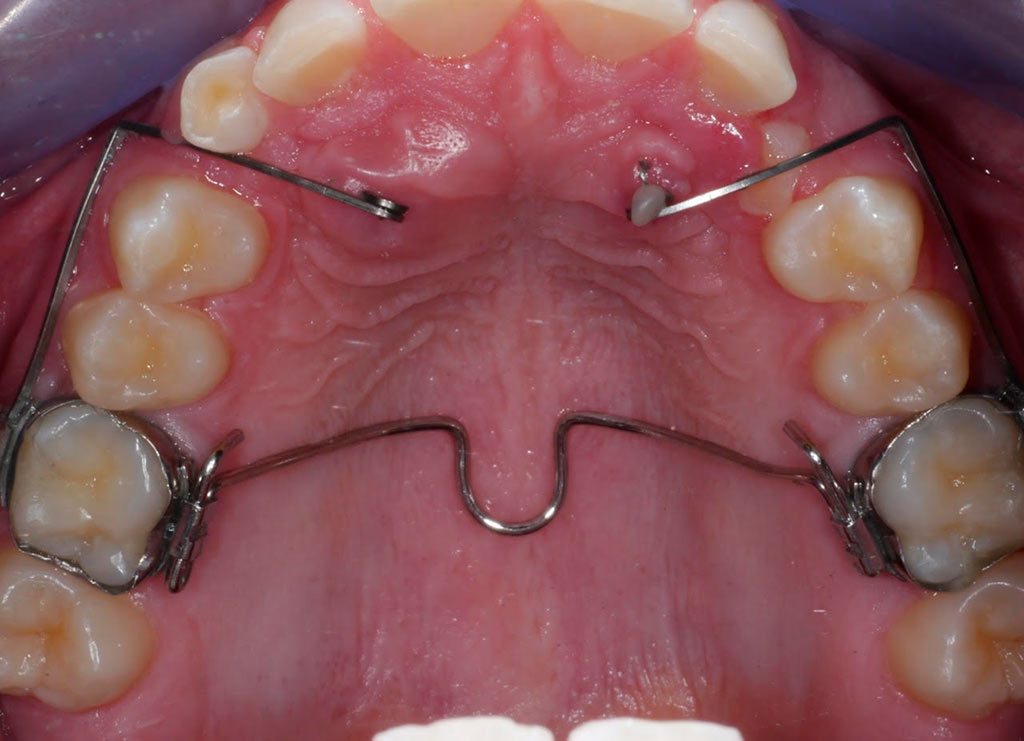

Tracción de canino con k9